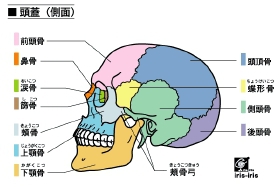

肩こり→(四十肩、五十肩)、腰痛→(ギックリ腰、腰椎ヘルニア、座骨神経痛)

姿勢(猫背、O脚、骨盤、外反拇趾、側湾症)→内臓不調 膝痛→(水がたまる、リウマチ)